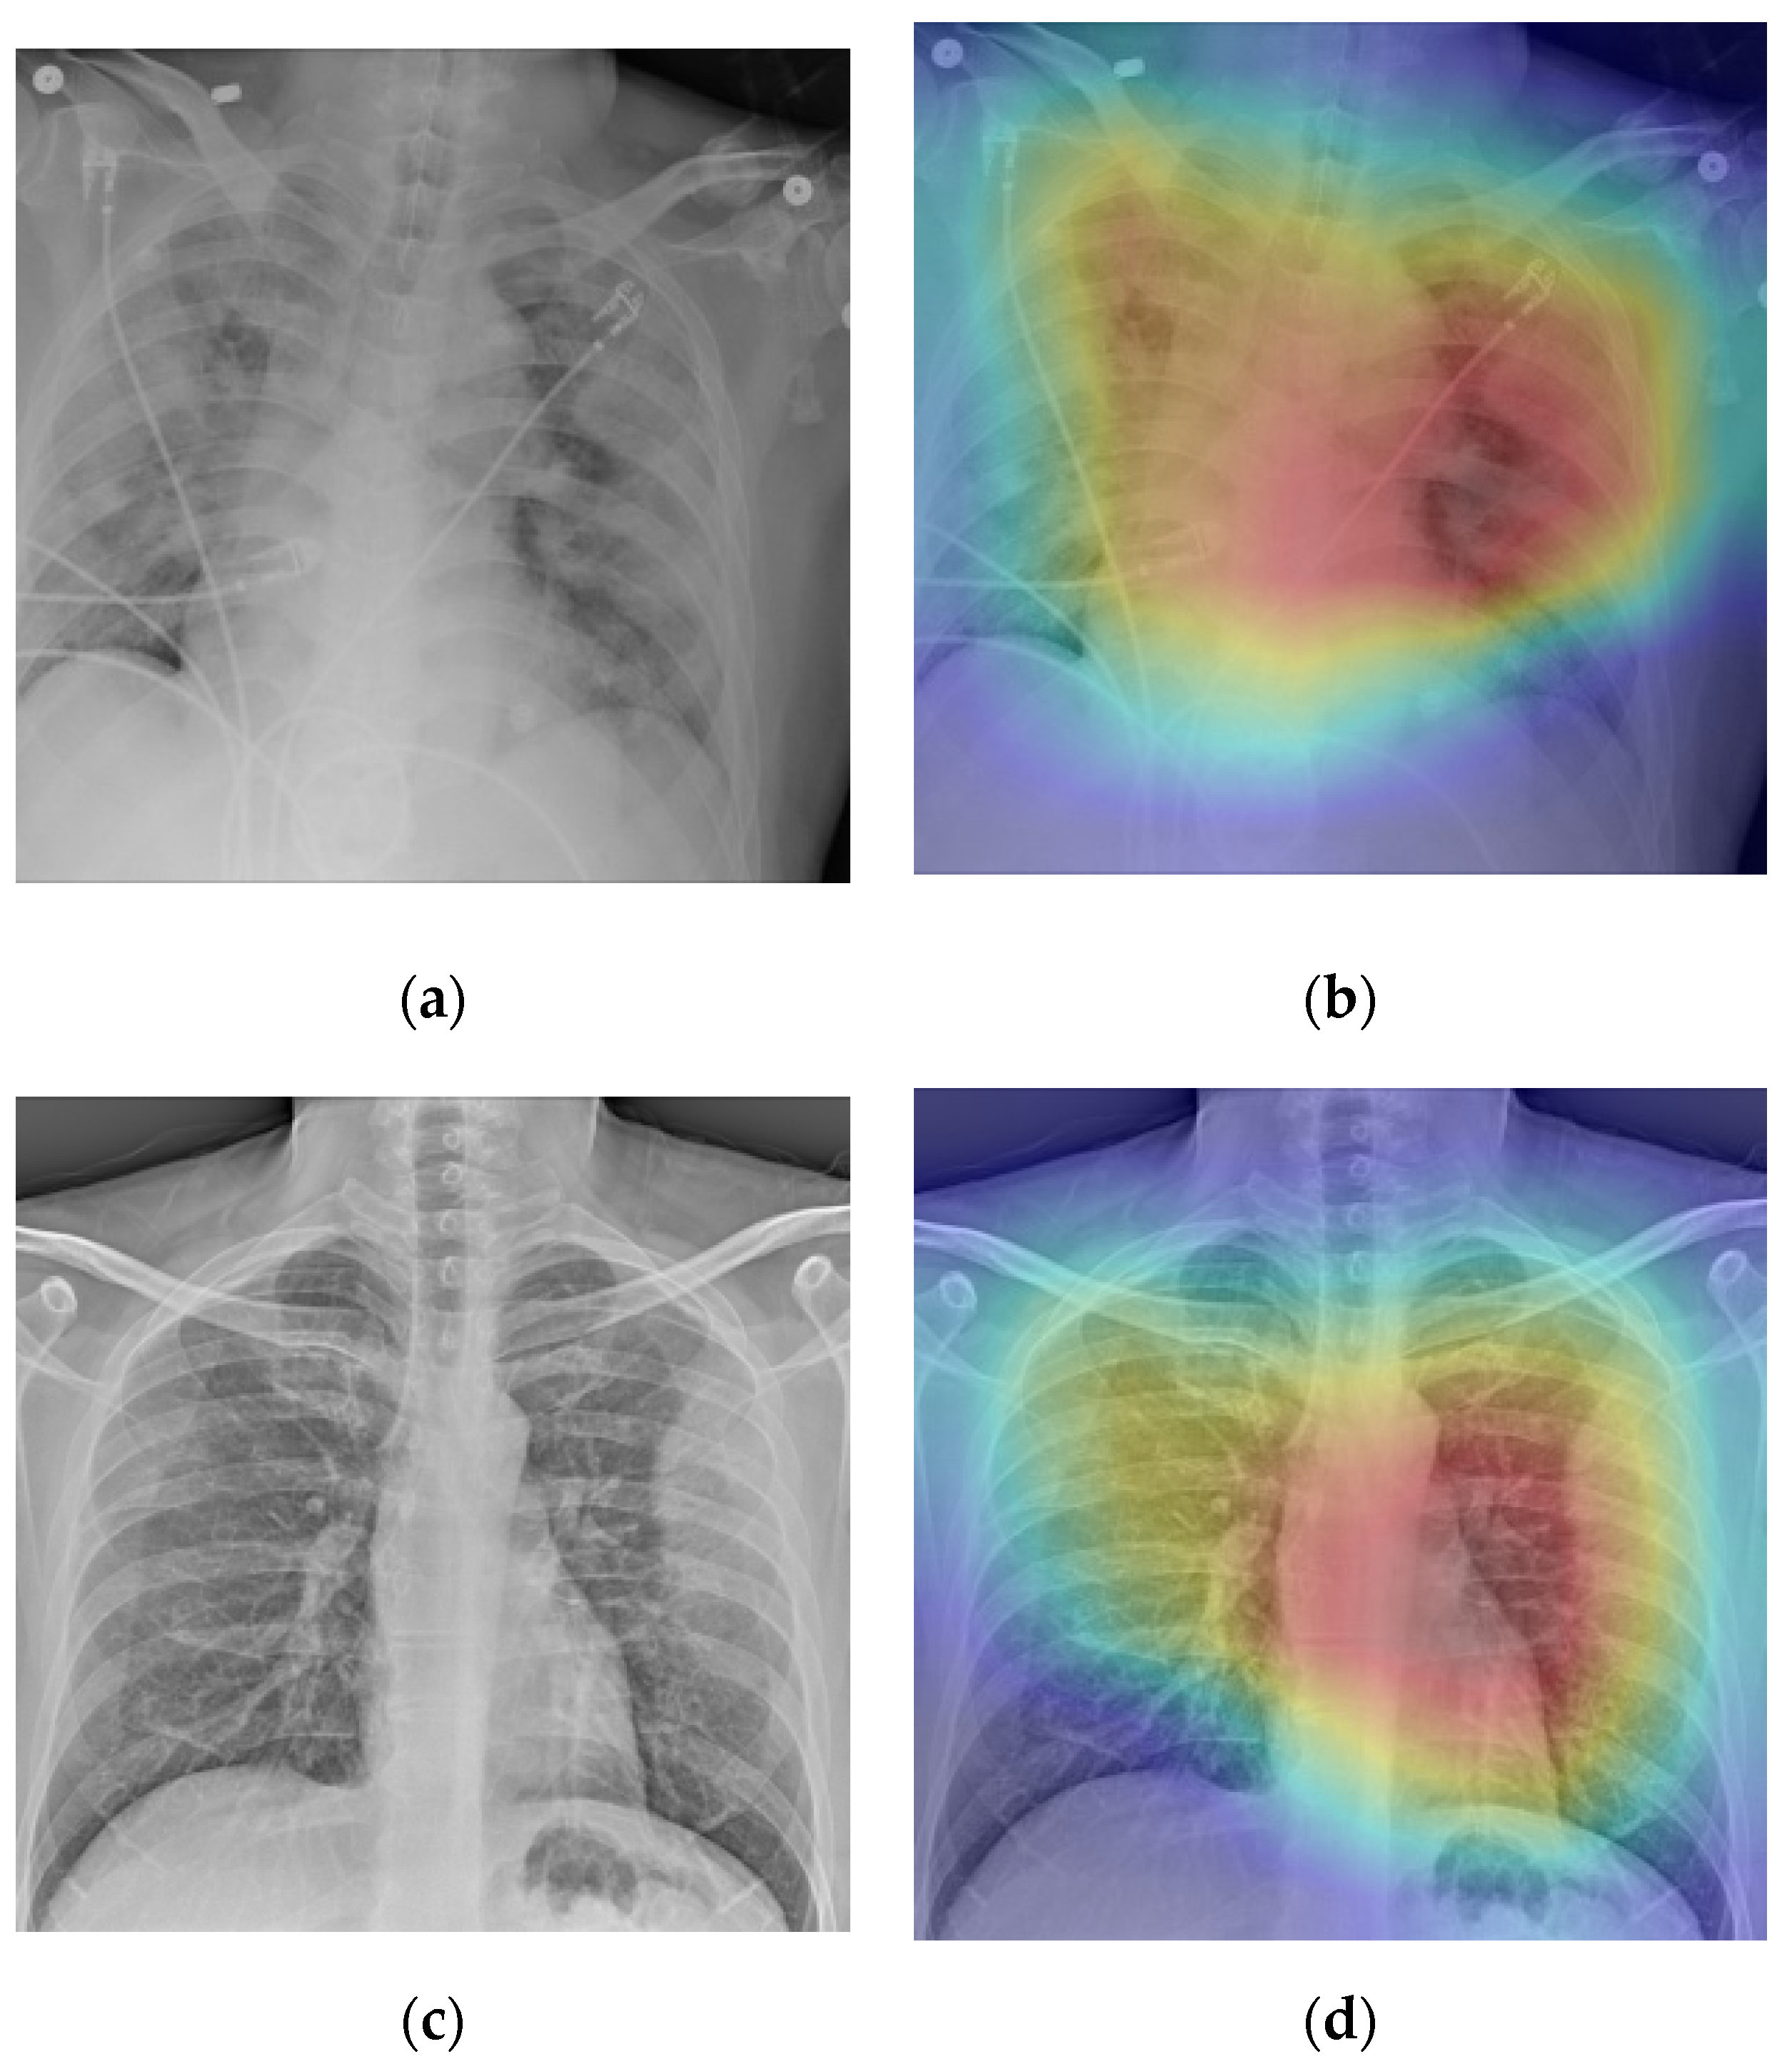

3.5. Screening and Localization

- Grad-CAM generation for test examples.

5.4. Disease Screening